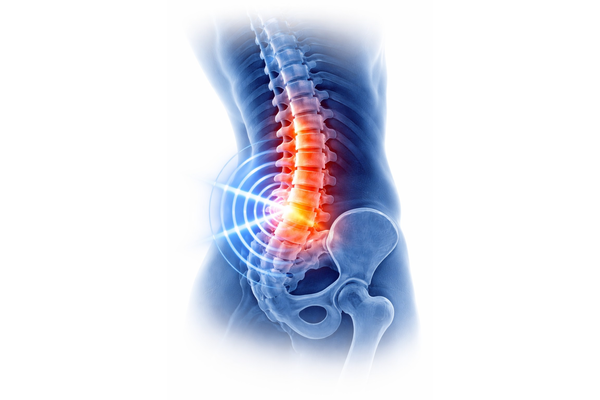

HUENIC CARE delivers advanced, non‑surgical spine care focused on relieving pain, restoring mobility and improving long‑term spinal function. Our technology‑driven approach supports facet joint health, intervertebral disc integrity and spinal alignment while addressing challenges such as disc degeneration, disc bulge‑related compression, post‑surgical discomfort and chronic lower back pain.

By combining targeted regenerative stimulation with structured rehabilitation, we help individuals regain stability, reduce dependency on surgery and return to daily activities with confidence.

Pain & Mobility Restoration

- Chronic back pain relief

- Lumbago support

- Long‑term spine recovery